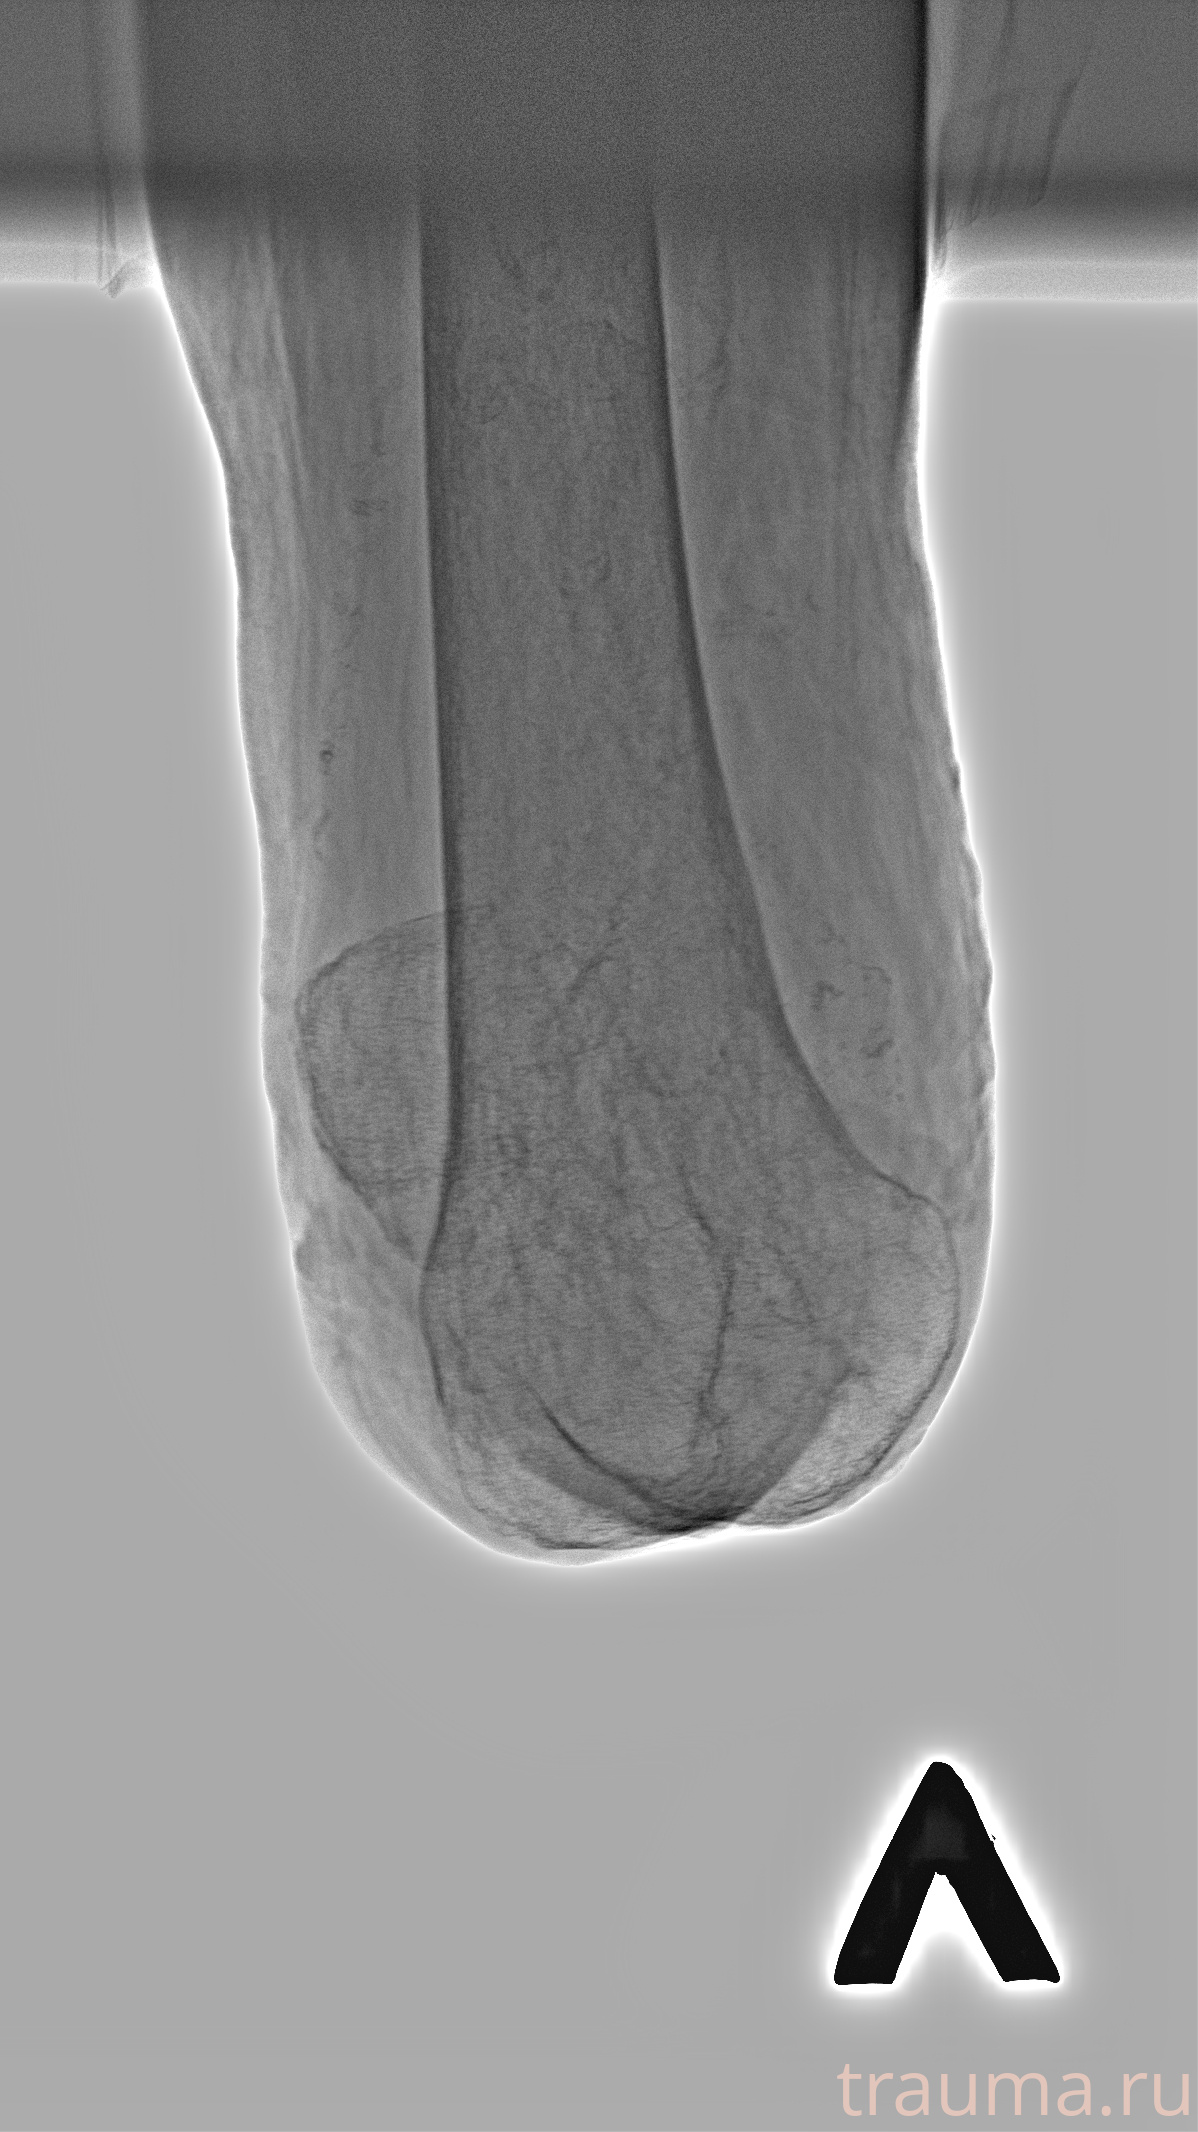

Рентгенограммы

Рентген на дому: по вашему адресу приезжает врач-рентгенолог, травматолог-ортопед с мобильным рентгеновским аппаратом, проводит диагностику травмы или заболевания, делает необходимые рентгенограммы, дает рекомендации по дальнейшему лечению. Получить качественные снимки в домашних условиях возможно благодаря уникальной методике, разработанной МосРентген Центром для института  Склифосовского